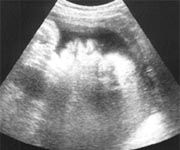

まるまると大きくなった赤ちゃんの多くは、頭を下にした姿勢で子宮の中で窮屈に手足を曲げています。苦しくないか心配になりますが、窮屈なりに赤ちゃんは最も居心地のよい姿勢に落ち着いています。自由に遊泳していた時にからまったのでしょうか。首や体に臍帯(さいたい)を巻き付けている赤ちゃんもいます。カラードップラーという超音波検査では、臍帯の血液の流れを観察できます。からまっていても臍帯にはきちんと血液が流れて、酸素や栄養が赤ちゃんに届いているのがわかれば安心できます。あわせて、出産の時には、赤ちゃんはママの子宮の中にいたそのままの姿勢で生まれてくるのが最も安全ということがわかっています。つまり、狭い子宮の中でかなり窮屈でも、赤ちゃんにとっては安全で心配のない姿勢というわけなのです。